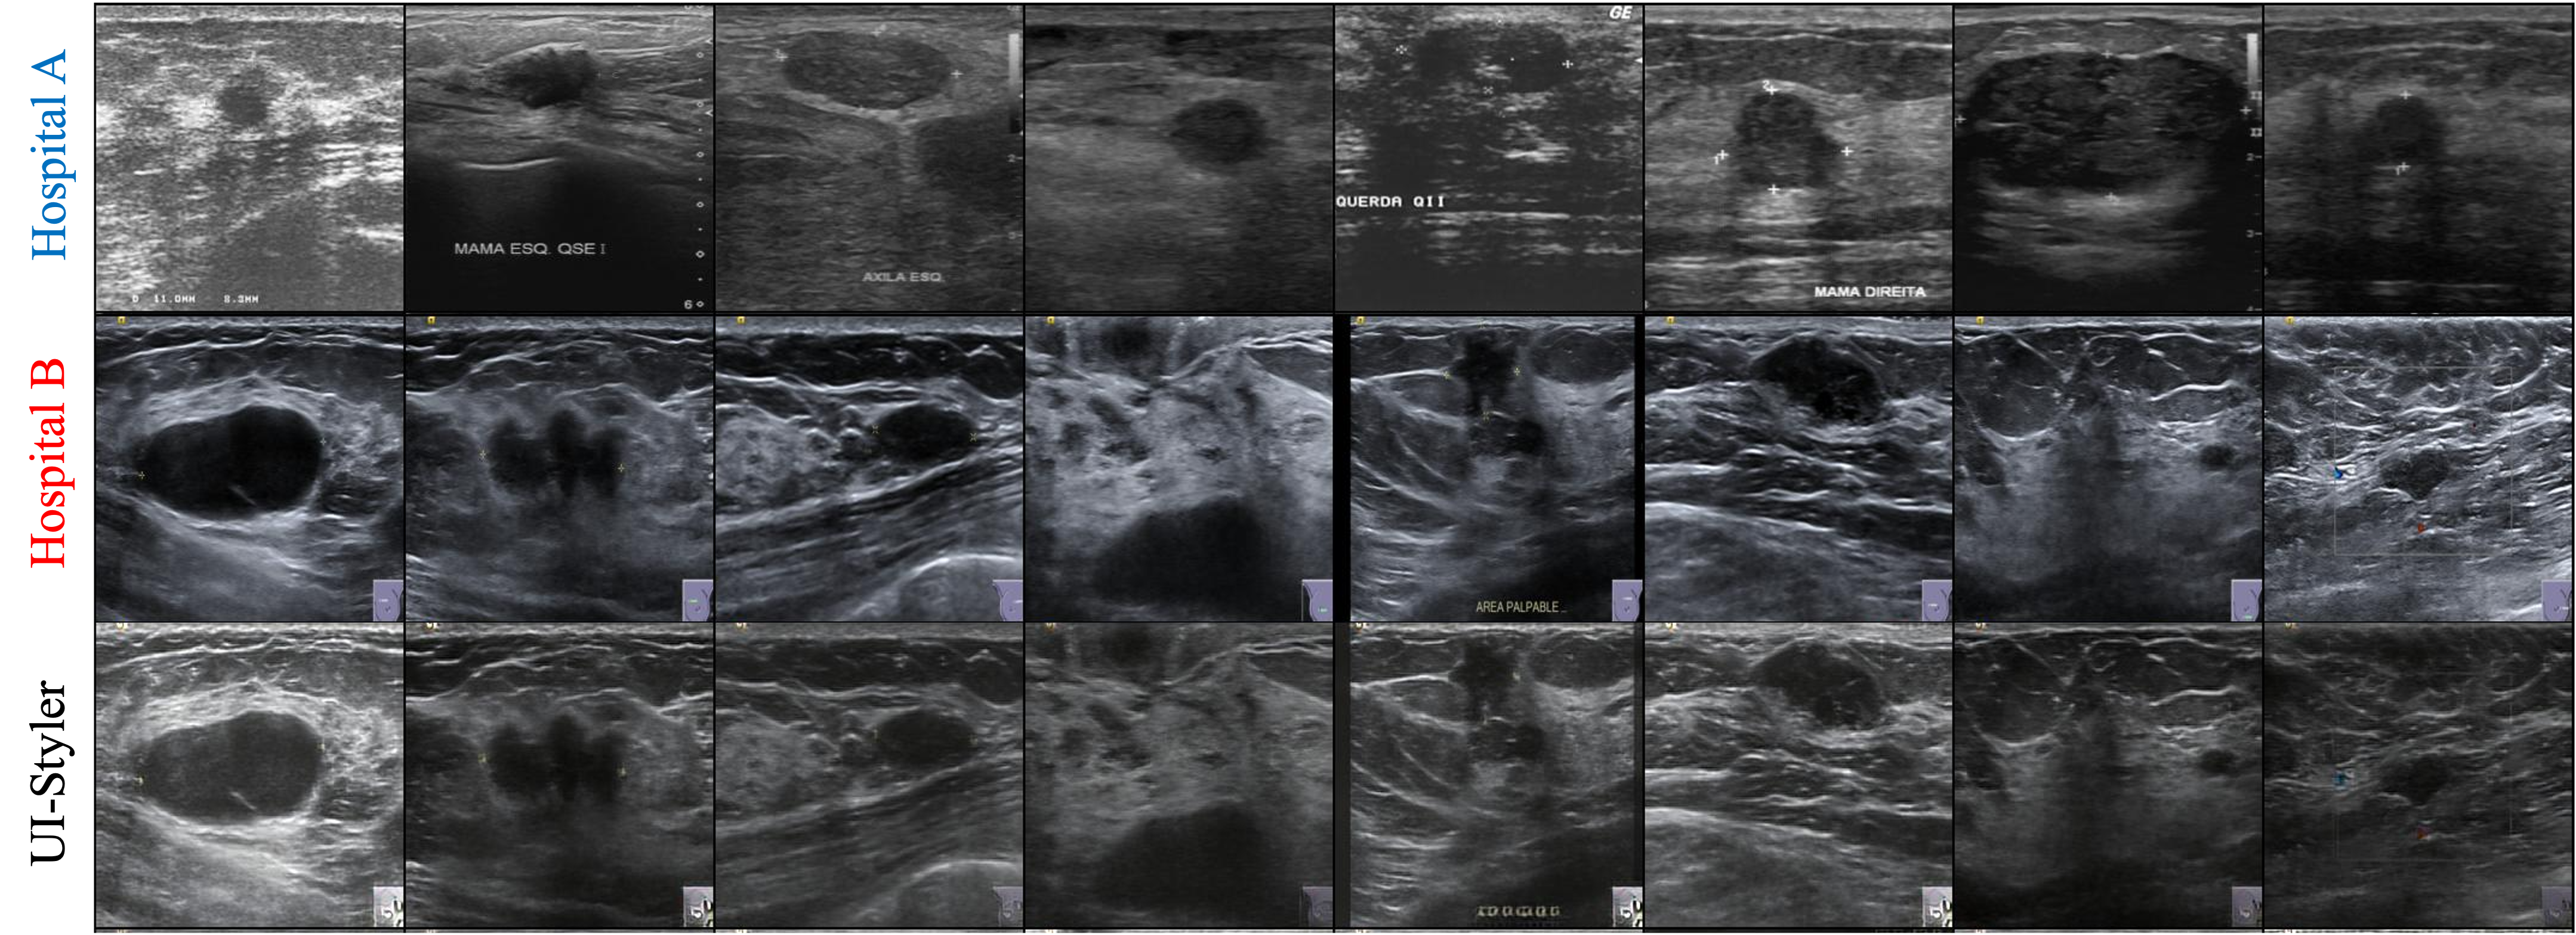

🖼️ Visual Results